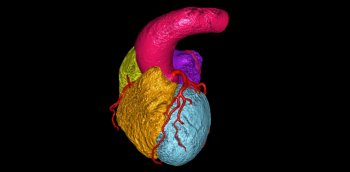

TC coronario en urgencias

El dolor torácico agudo es una causa de consulta frecuente en los Servicios de Urgencias y su evaluación continúa siendo uno de los mayores retos a los que se enfrentan los médicos que los atienden. En Estados Unidos más de 8 millones de pacientes acuden a los...